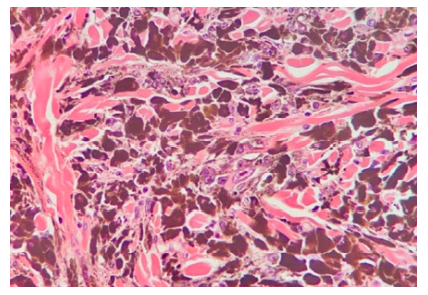

Histological findings of PEM include: wedge-shaped symmetrical configuration; central increased cellularity; epithelioid cells, dendritic cells and melanophages.1 Clusters of large multinucleated cells with vesicular nuclei and macronucleoli (Reed-Sternberg-like) are the most distinct finding in PEM.1

The lesion was promptly excised. Histopathology showed a circumscribed, symmetrical, wedge-shaped dermal proliferation composed predominantly of pigmented epithelioid cells and dendritic cells. The cells had large nuclei and prominent nucleoli. In some areas multinucleated cells were found. No mitotic figures were identified.